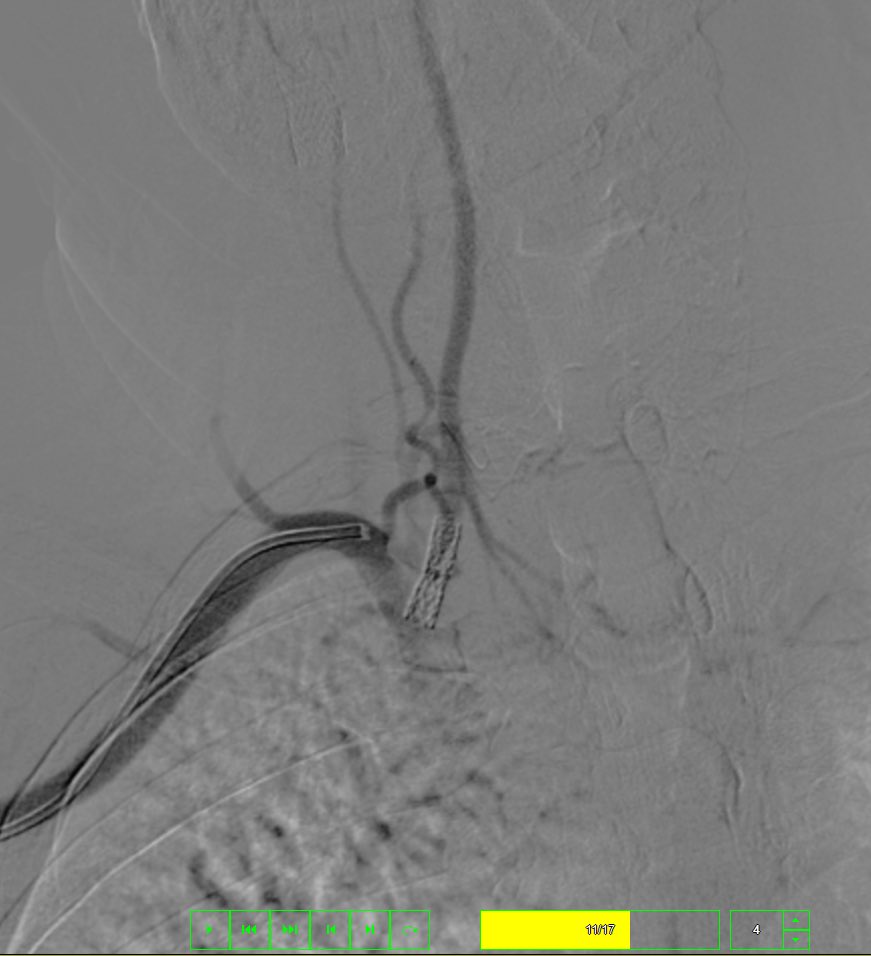

Case : AVM of leg with Pain & Limp.

Rx : AVM Embolization with Glue

#avm #embolization #irad #interventionalradiology #MedTwitter #Mumbai @ISVIRIndia @JVIRmedia @SIRspecialists @SIRRFS @cirsesociety @ApolloHosMumbai